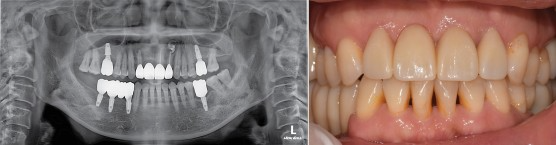

#12X21.22 CR 제작, Fistula 없어짐